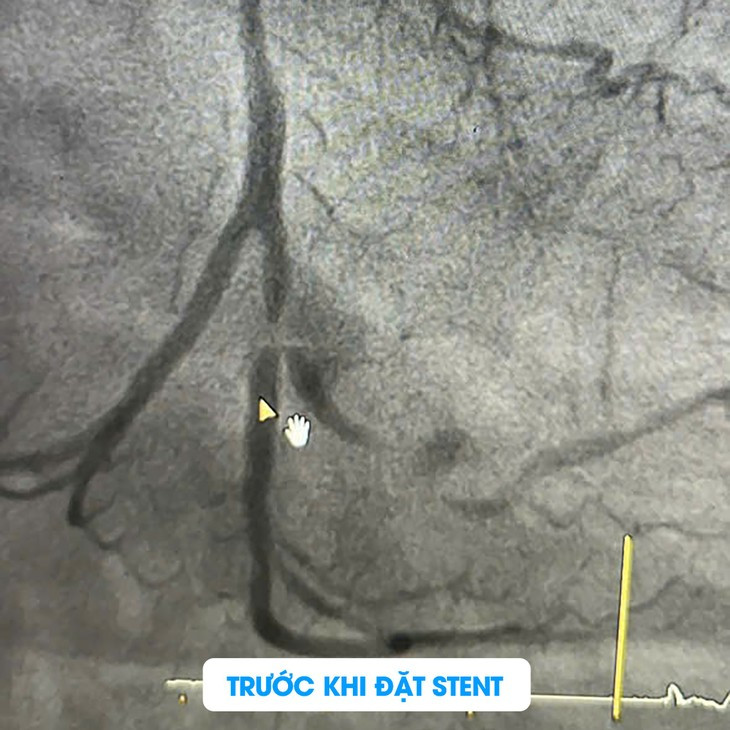

Sau khi nhập viện, bệnh nhân đã được tiến hành chụp mạch vành qua da để xác định tình trạng tắc nghẽn và xơ vữa. Kết quả chụp cho thấy bệnh nhân có tổn thương cả 3 nhánh động mạch vành với các mức độ khác nhau:

Thân chung động mạch vành trái (LM): Hẹp 30%.

Động mạch liên thất trước (LAD): Hẹp 40 - 50% ở đoạn gần, 40% ở đoạn giữa và xa, có nhiều vôi hóa.

Động mạch mũ (LCx): Hẹp 60% ở đoạn gần và hẹp nặng tới 99% tại đoạn xa ở vị trí chia đôi, có vôi hóa nhiều.

Động mạch sau (PDA): Hẹp 60%.

Sau khi hội chẩn kỹ lưỡng và cân nhắc đến các bệnh lý nền của bệnh nhân, bác sĩ Peter và các cộng sự đã quyết định thực hiện can thiệp nong đặt stent tại động mạch LCx, đoạn gần (LCx(d)), nơi có mức độ tổn thương hẹp nặng và nguy hiểm. Quy trình này giúp tái thông dòng máu đến vùng cơ tim bị thiếu máu, ngăn ngừa nguy cơ nhồi máu cơ tim tái phát.